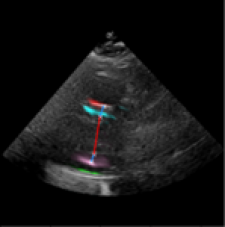

Left Ventricular Hypertrophy (LVH), one of the leading predictors of adverse cardiovascular outcomes, is the condition where heart’s mass abnormally increases secondary to anatomical changes in the Left Ventricle (LV) [10]. These anatomical changes include an increase in the septal and LV wall thickness, and the enlargement of the LV chamber. More specifically, Inter-Ventricular Septal (IVS), LV Posterior Wall (LVPW) and LV Internal Diameter (LVID) are assessed to investigate LVH and the risk of heart failure [21]. As shown in Figure 1 (a), four landmarks on a parasternal long axis (PLAX) echo frame can characterize IVS, LVPW and LVID, and allow cardiac function assessment. To automate this, machine learning-based (ML) landmark detection methods have gained traction.

It is difficult for such ML models to achieve high accuracy due to the sparsity of positive training signals (four or six) pertaining to the correct pixel locations. In an attempt to address this, previous works use 2D Gaussian distributions to smooth the ground truth landmarks of the LV [9, 13, 18]. However, as shown in Figure 1 (b), for LV landmark detection where landmarks are located at the wall boundaries (as illustrated by the dashed line), we argue that an isotropic Gaussian label smoothing approach confuses the model by being agnostic to the structural information of the echo frame and penalizing the model similarly whether the predictions are perpendicular or along the LV walls.